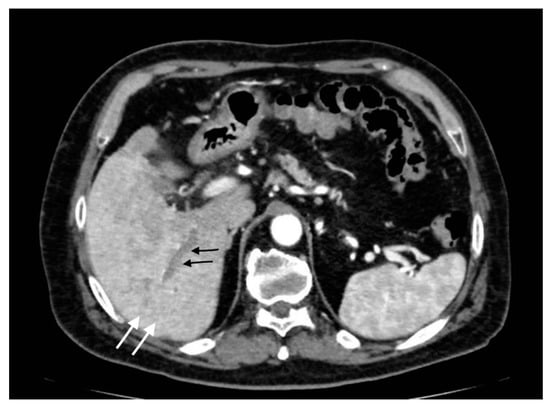

Acute portal vein thrombosis is an uncommon condition caused by the formation of a thrombus within the portal vein, as the inflammatory insult persists. Besides acute cholecystitis, it could be diagnosed as a complication of many other conditions, such as diverticulitis, urinary and pelvic infections, and malignancies [23,24]. Symptoms may be subtle, often masked by the underlying condition. CT and US are the main modalities for the acute assessment of PVT. The lack of enhancement within the vein lumen and an enlarged portal vein are the two main classic imaging CT features [24,25]. CT, unlike US, is also able to evaluate the extension of the thrombus and to detect associated findings, such as hepatic hyperemia (Figure 10), or complications, such as enteric ischemia or intra-abdominal collections [24]. Suppurative thrombosis of the portal vein, also known as pylephlebitis, is a life-threatening condition that requires early diagnosis and therapeutic assessment. The exact pathogenesis is not well known, but it is proven that specific bacterial species, such as Bacteroides Fragilis, play a key role in favoring a protrombothic state [26] and the clinical features of sepsis. As regards PVT, CT evaluation is meaningfully superior to ultrasonography for the diagnosis. Consequent to hepatic artery overflow due to PVT occlusion, transient contrast enhancement of the adjacent hepatic parenchyma during the arterial phase may occur, as well as hepatic microabscesses (Figure 11) [27]. Although not seen in most cases, CT may detect the presence of air within the thrombus as a hypodense focus within the thrombosed PV [24].

Figure 11.

Pylephlebitis in cholecystitis exacerbation: (a) massive thrombosis of the portal bifurcation with hyperdensity of portal walls due to pylephlebitis (white arrows) and inhomogeneous attenuation of liver parenchyma in arterial CT scan due to vascular occlusion; (b) axial scan: irregular thickening of cholecystic walls with contrast enhancement of liver parenchyma due to pericholecystic edema.